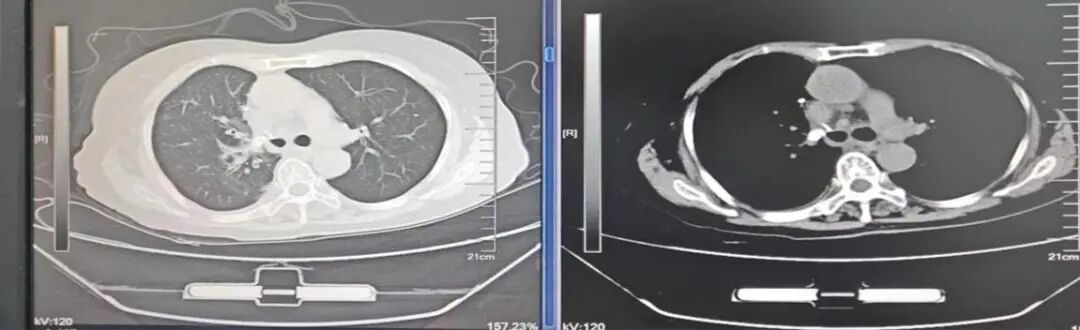

(三)新辅助治疗后的肺癌微创根治术

偏晚期的肺癌手术机会渺茫,新辅助治疗(术前免疫、靶向、化疗等)可让患者重获根治性手术机会。如图:7.7cm左上肺癌,若直接手术,可能无法切除或被迫切除左全肺。新辅助免疫+化疗4个疗程后,病变由7.7cm缩小到4cm,在单孔胸腔镜下肺动脉成形完成左上肺癌根治术(左上肺叶切除+淋巴结清扫),不仅只切除了左上肺保留住了左下肺,而且术后病理检查显示术前用药后残存癌细胞比例仅残存6%,也就是说4cm肿块里面94%的组织已经没有癌细胞,远期疗效更佳。